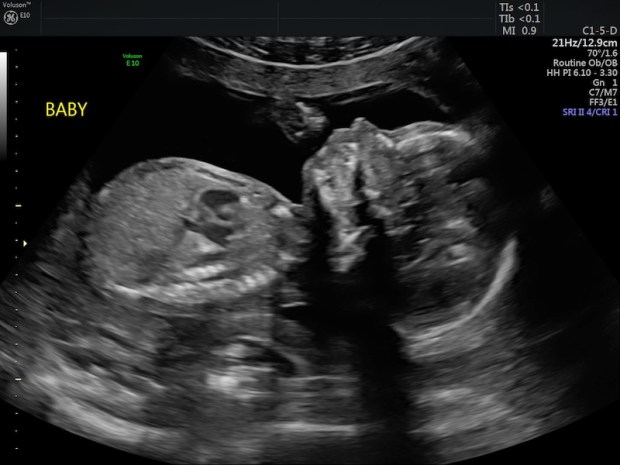

We are officially past the halfway point in the pregnancy. It feels like it’s flying by! At the same time, November also feels eons away. It’s a weird thing! Our anatomy scan went well. Baby boy is doing great and it was so lovely to see him kicking and rolling around!